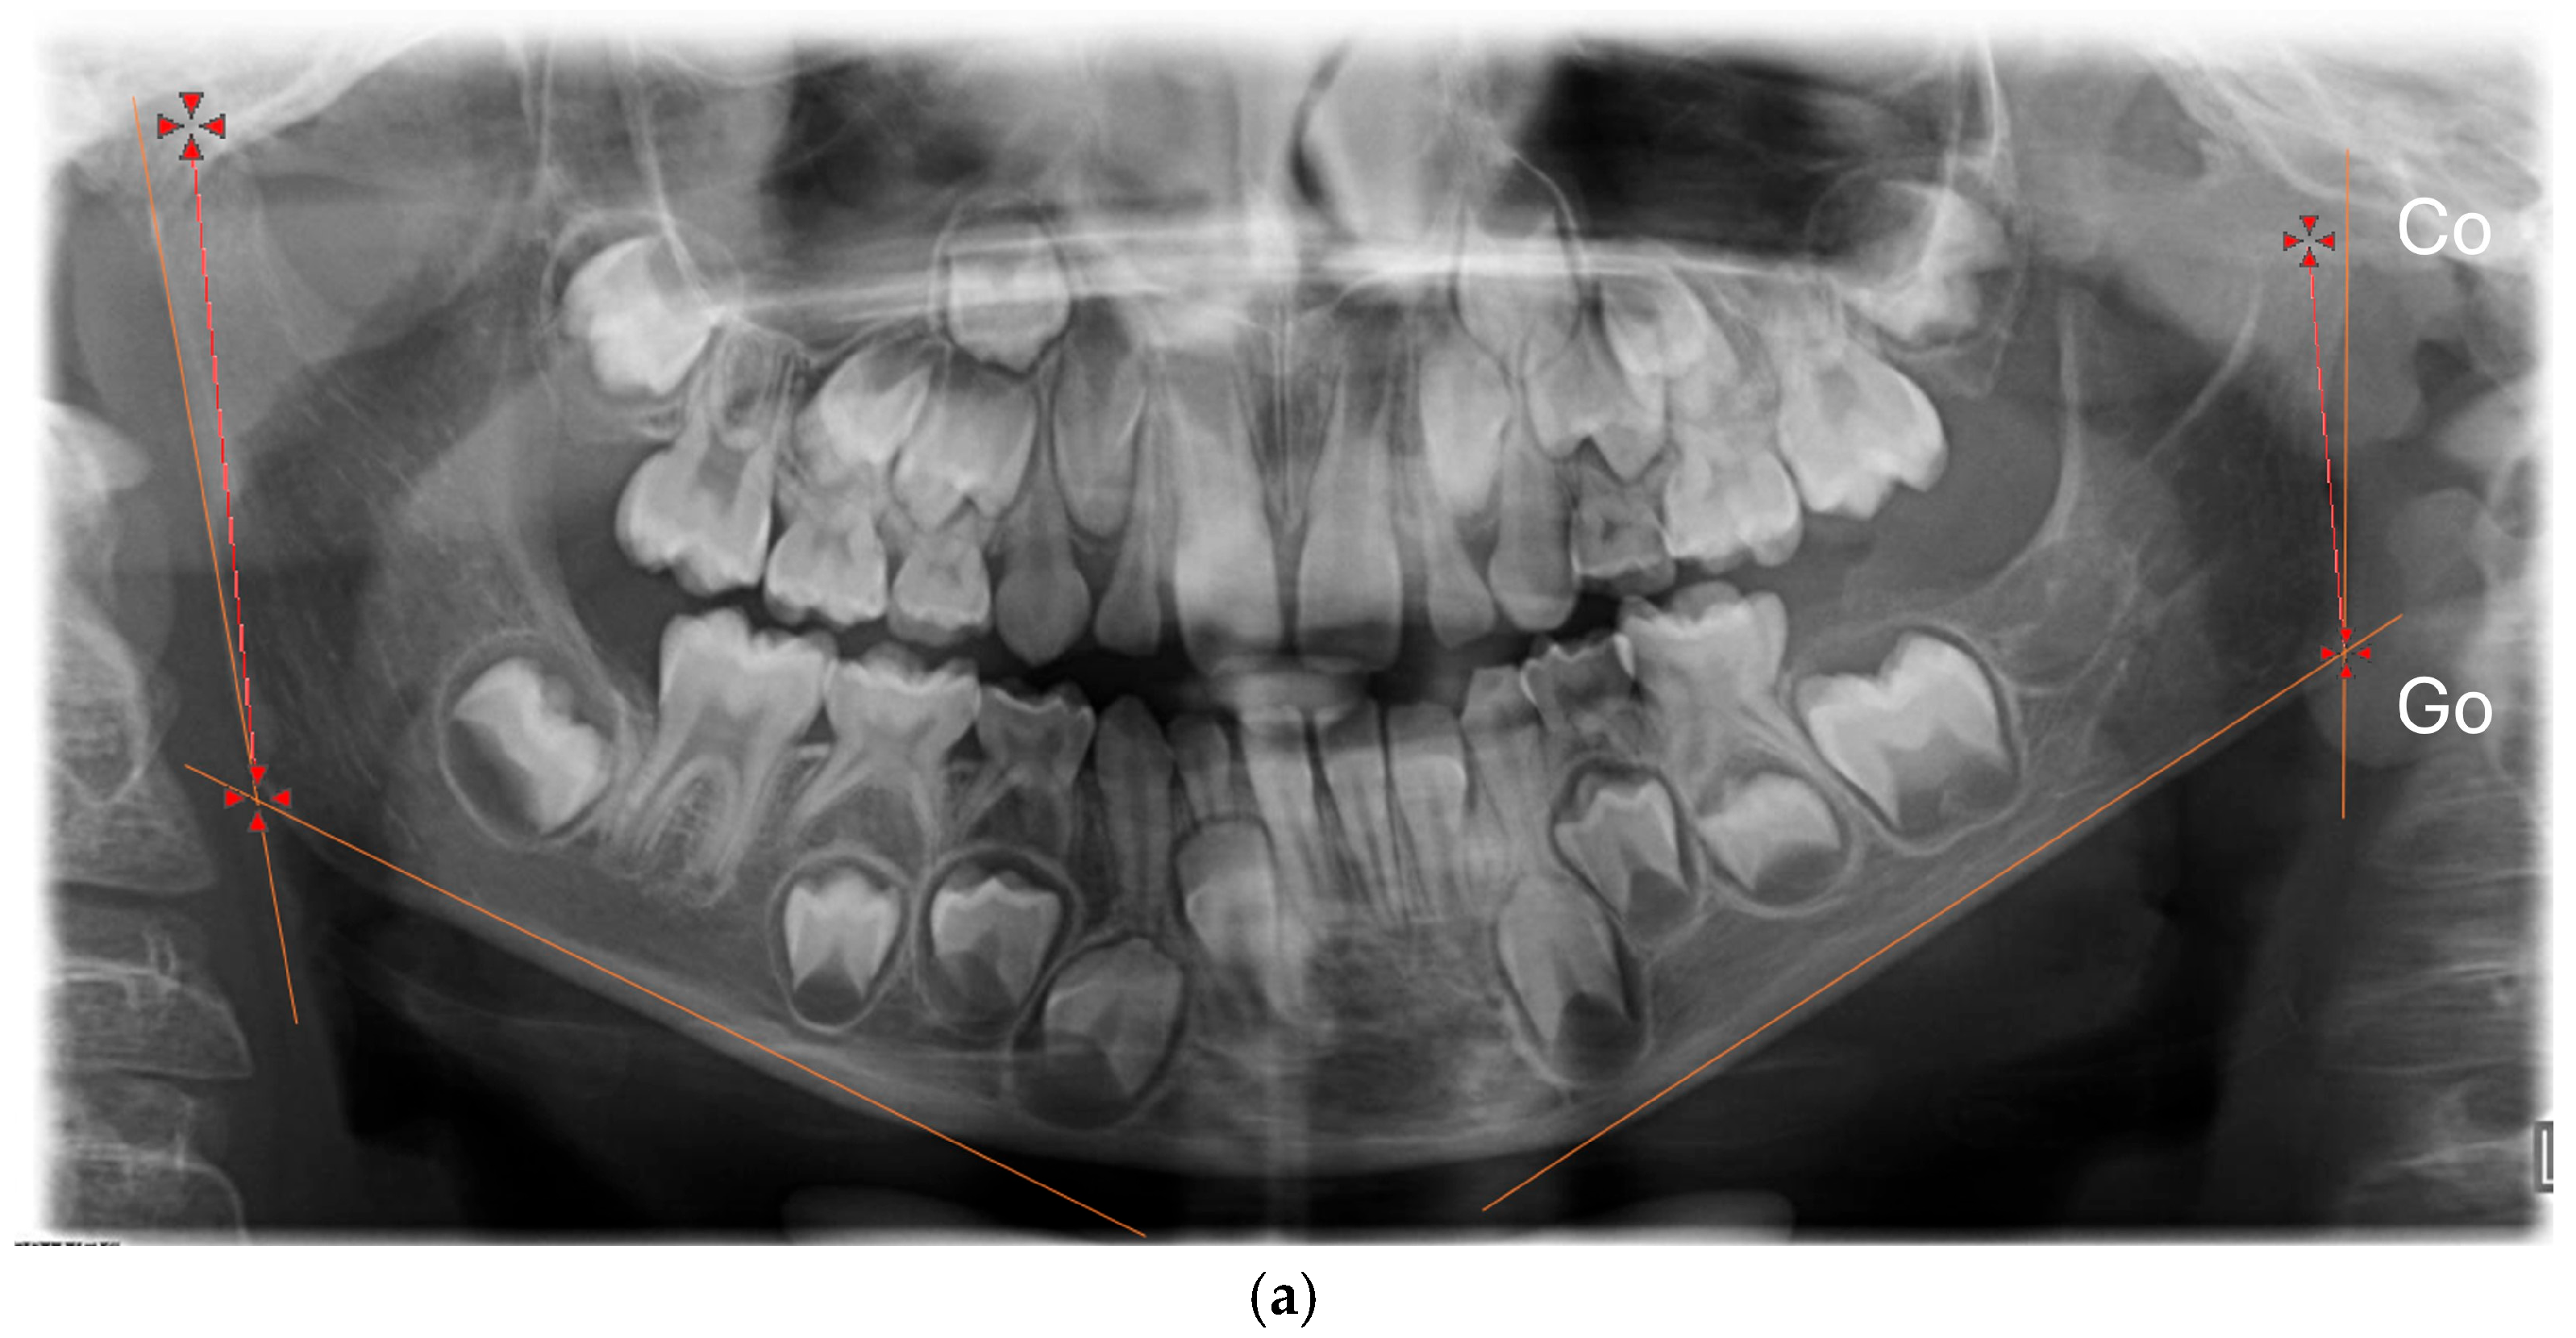

For each patient, sex, side of the CFM, degree of severity, classified according to the OMENS system, and age at the start and at the end of the functional treatment were collected. We collected the panoramic radiographs of patients at the beginning (T0) and at the end (T1) of the functional therapy. All the radiographs were digitized, together with a 5 cm ruler as reference. The “Meazure” measurement free software (version 4.0) was used to calibrate every digital image; after calibration, two measures were taken on the right and on the left side (Figure 1):

• The vertical height of the mandibular ramus (Co-Go), from the condylion (the uppermost posterior point of the condyle) to the gonion (the lowest and posterior point on the gonial angle) [16,17,18].

• The vertical length of the condyle, from the condylion to a vertical point on the plane passing by the sigmoid notch (Co-IS) (Figure 1).

Figure 1. Measurements taken in the study. (a) Condylion–gonion (Co-Go); (b) condylion–sigmoid notch (Co-IS).